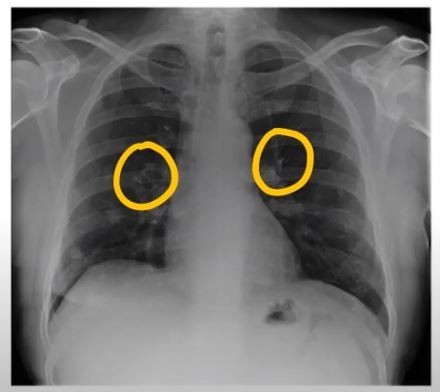

폐암 초기증상 폐암은 초기 증상이 감기나 다른 호흡기 질환과 비슷해 간과하기 쉽습니다. 하지만 조기 발견이 치료에 매우 중요하기 때문에, 미묘한 변화라도 놓치지 않는 것이 중요합니다. 지금부터 폐암의 주요 초기 증상들을 꼼꼼히 살펴보고, 건강을 지키는 첫걸음을 함께 시작해 볼까요?

폐암 초기에는 특별한 증상이 없는 경우가 많지만, 암이 진행되면서 다양한 신호를 보낼 수 있습니다. 다음은 폐암 환자들이 흔히 경험하는 10가지 주요 초기 증상입니다.